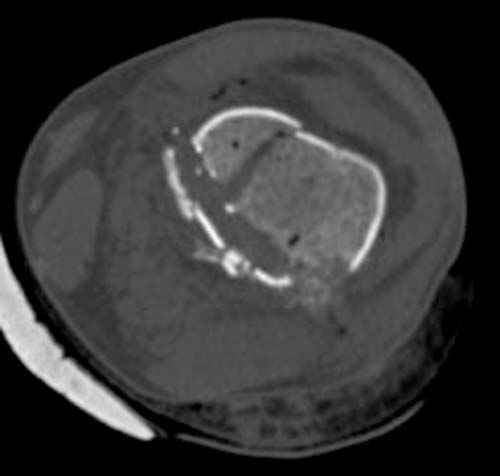

У молодого человека огнестрельное слепое ранение н/3 правого бедра. Поступил в клинику с внутрисуставным многооскольчатым Т-отразным переломом дистального отдела бедренной кости. Дополнительно на  СТ-исследовании обнаружен перелом внутреннего мыщелка Hoffa со смещением.<br><br>

Больной взят в операционную на второй день, где из небольшого медиального доступа выполнена артротомия коленного сустава. Произведена репозиция отломков, фиксация винтами. Попутно удалена пуля. Первым делом была достигнута репозиция медиального мыщелка (перелома Hoffa, где коронарная плоскость перелома трудно поддается закрытой репозиции и фиксации. ) Затем была достигнута идеальная репозиция суставной поверхности бедра и фиксация компрессирующими headless  screws.<br><br>

Дистальный отдел бедра был дополнительно фиксирован buttress пластиной с медиальной стороны из того же разреза. Для усиления фиксации латеральной колонны -  с латеральной стороны закрытым способом из минидоступа установлена еще buttress plate.  Пулевой канал дополнительно не подвергался хирургической обработке.<br><br>